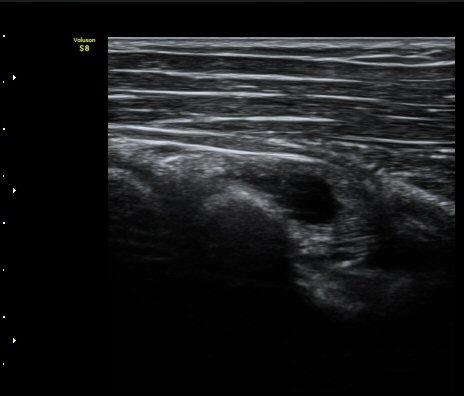

ŽÃËÀÚ¸¦ Á» ´õ ¸»´ÜÀ¸·Î À̵¿ÇÏ´Ï ³¶Á¾Àº ´õ Å©°Ô °üÂûµÈ´Ù(±×¸² 3, 4).

¿ä°ñÀ» Á¾´Ü¸éÀ¸·Î °üÂûÇÏ´Ï ¿ä°ñ ±ÙÀ§ºÎ Ç¥Ãþ¿¡ ³¶Á¾ÀÌ È®Àεǰí(±×¸² 5) ŽÃËÀÚ¸¦

Á¶ÀýÇÏ´Ï Èİñ°ß½Å°æÀÇ Á¾´Ü¸é À̹ÌÁö°¡ °üÂûµÇ´Âµ¥ ³¶Á¾¿¡ ÀÇÇØ Ç¥ÃþÀ¸·Î ÀüÀ§µÇ¾î

ÀÖ´Ù(±×¸² 6,7). ±×¸² 8. ³¶Á¾°ú Èİñ°£½Å°æ ÁÖÀ§¾Ö¼­ °üÂûµÇ´Â µ¿¸Æ.